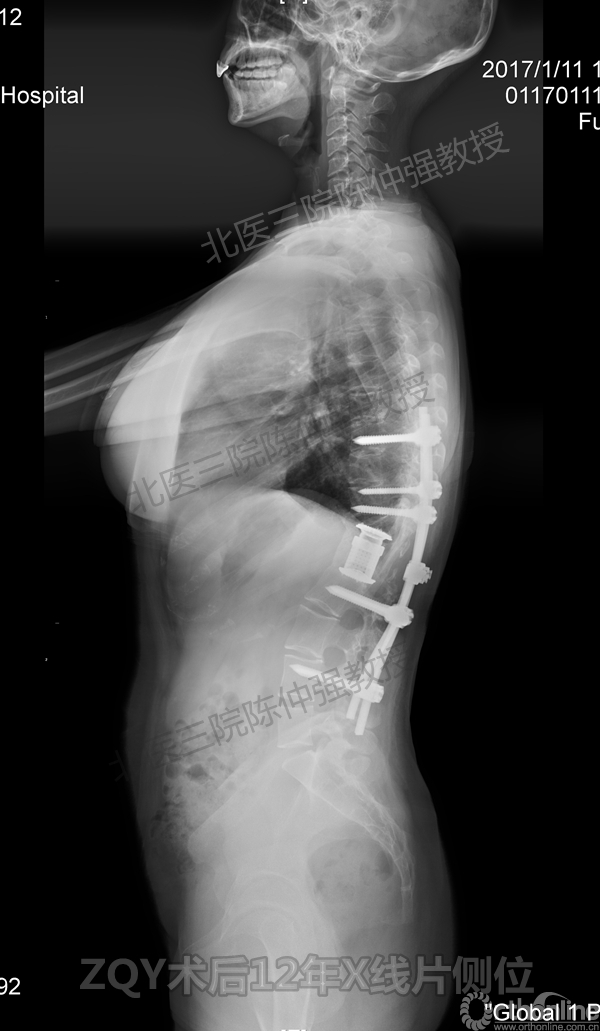

ZQY术后12年

患者女性17岁,胸腰椎陈旧结核性侧后凸畸形,局部呈“麻花状”扭转,无神经功能受损表现。2005年,陈仲强教授带领团队实施后路+侧前方联合入路脊柱节段切除、双轴旋转矫形术。术后患者外观显著改善,神经功能正常。术后随访证实患者截骨矫形节段骨性融合良好,矫形效果持续良好。